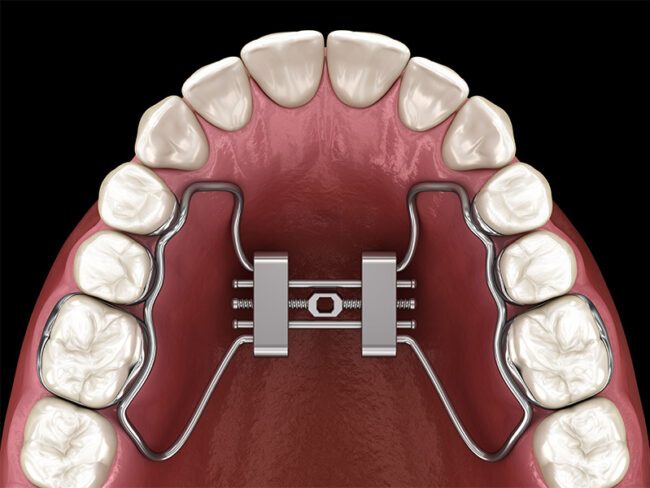

Un sorriso allineato non è soltanto una questione estetica: è anche sinonimo di salute, equilibrio e benessere. L’ortodonzia fissa è una delle soluzioni più affidabili per correggere i disallineamenti dentali e migliorare la funzionalità della bocca, restituendo ai pazienti un sorriso armonioso e una masticazione corretta. Cos’è e come funziona l’ortodonzia fissa L’ortodonzia fissa utilizza un…